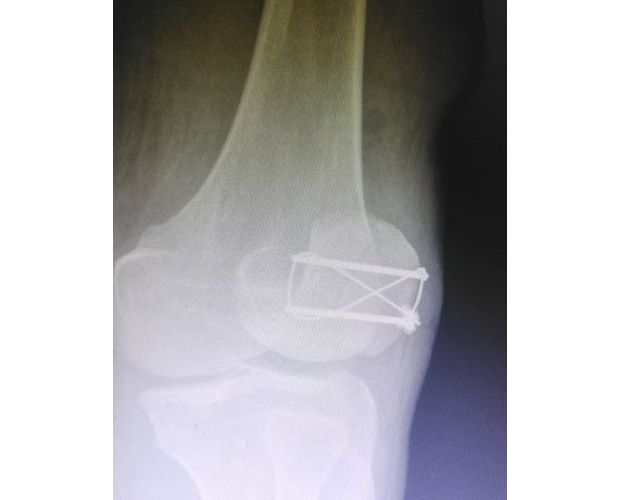

精湛施術 安全有序,守護患者健康

手術現場,徐三軍主任憑借多年積累的臨床經驗和嫻熟的手術技巧,精準完成骨折復位、鋼板內固定、傷口縫合等一系列關鍵操作,動作規范流暢、精準高效,最大限度減少手術創傷。該院外科醫護團隊全程密切配合、協同發力,嚴格按照手術規范操作,全程嚴密監測患者心率、血壓等生命體征,及時應對術中各類突發情況,全力保障手術安全。此次手術全程順利,術中出血量少,患者生命體征始終平穩,術后患者順利安返病房,為后續康復治療奠定了堅實基礎。